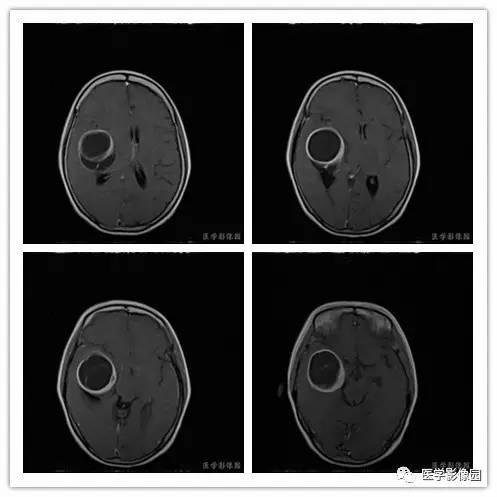

影像学表现:右侧颞叶深部区见一长T1、长T2囊样信号,成明显环形强化、未见明确结节影,没有FLAIR和DWI图,内见分隔,边界较清,周围水肿不明显,右侧脑室明显受压、颞角扩大,右侧脑沟明显变浅,脑中线结果向左偏移。

1.肿瘤主要表现为等长T1 、等长T2 混杂信号影,偶可见短T1 或短T2 信号影,注药后,肿瘤增强明显但不均匀;

2.外形呈不规则分叶状;

3.半数以上的肿瘤与硬膜窄基底相连;

4.肿瘤内常可见血管流空影而见不到钙化影;